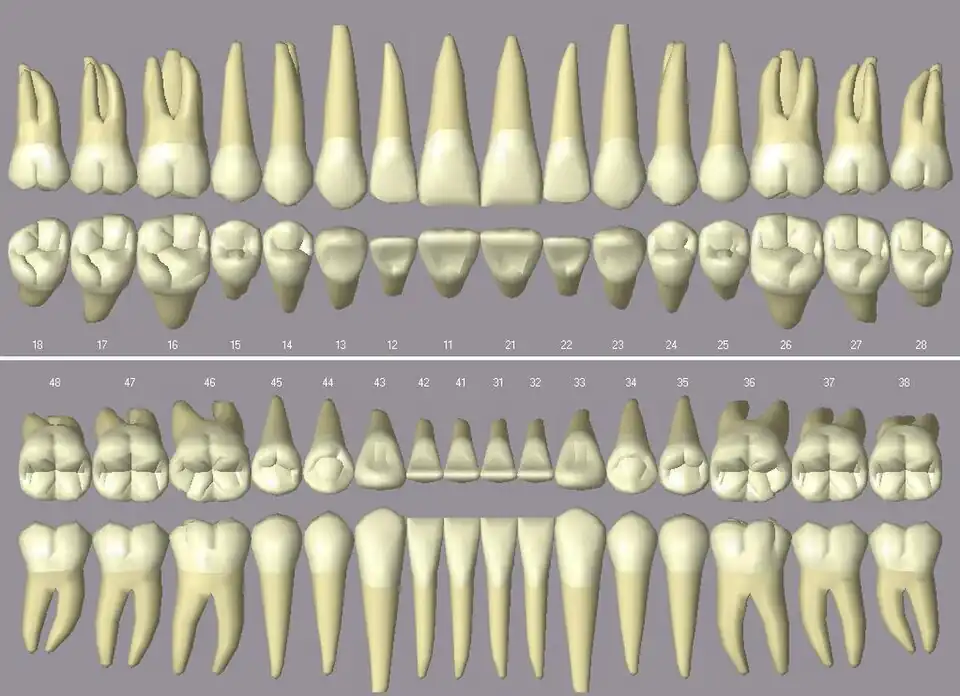

Der Mensch verfügt normalerweise über insgesamt 32 bleibende Zähne (inklusive der Weisheitszähne), jedoch können auch einzelne oder mehrere Zähne nicht angelegt sein: Hypodontie. Seltener liegt eine Überzahl von Zähnen vor: Hyperdontie. Das Milchgebiss umfasst 20 Milchzähne, jeweils 5 pro Quadrant. Alle Zähne im menschlichen Gebiss sind Zähne mit Zahnwurzel. Schneide- und Eckzähne bilden dabei die Frontzähne, Vormahl- und Mahlzähne die Seitenzähne (umgangssprachlich: Backenzähne).

Zahnbezeichnungen

Die Zähne des Menschen werden in der Zahnheilkunde durch verschiedene Zahnschemata eindeutig bezeichnet. International durchgesetzt hat sich seit 1970 das FDI-Schema der Fédération Dentaire Internationale. Jeder Zahn erhält eine Bezeichnung, die aus zwei Ziffern besteht. Die erste Ziffer bezeichnet den Quadranten, in dem sich der Zahn befindet. Die zweite Ziffer ist die Durchnummerierung der Zähne von der Mitte aus nach hinten.

Menschliche Zähne haben eindeutige Zahnmerkmale. Diese machen es möglich, nur anhand der Zahnform zu bestimmen, welche Position der Zahn im Gebiss eingenommen hat.

- Anhand des Winkelmerkmals, des Krümmungsmerkmals sowie des Wurzelmerkmals ist bestimmbar, ob der Zahn zur rechten oder linken Kieferhälfte gehört.

- Die Kronenflucht gibt Auskunft darüber, ob der Zahn zum Unter- oder zum Oberkiefer gehört.

- Daneben gibt es einmal das Zahnhalsmerkmal, das von vestibulär beurteilt wird. Hierbei ist der apikalste Punkt des labialen Zahnhalses nach distal verschoben. Dieses Merkmal tritt bei Frontzähnen, insbesondere bei den beiden mittleren Schneidezähnen auf. Ferner weisen die unteren Frontzähne distal im Wurzelbereich oftmals eine Eindellung, das Furchenmerkmal auf. Durch diese Konkavität lassen sich die unteren Schneidezähne der entsprechenden Seite zuordnen.[10]